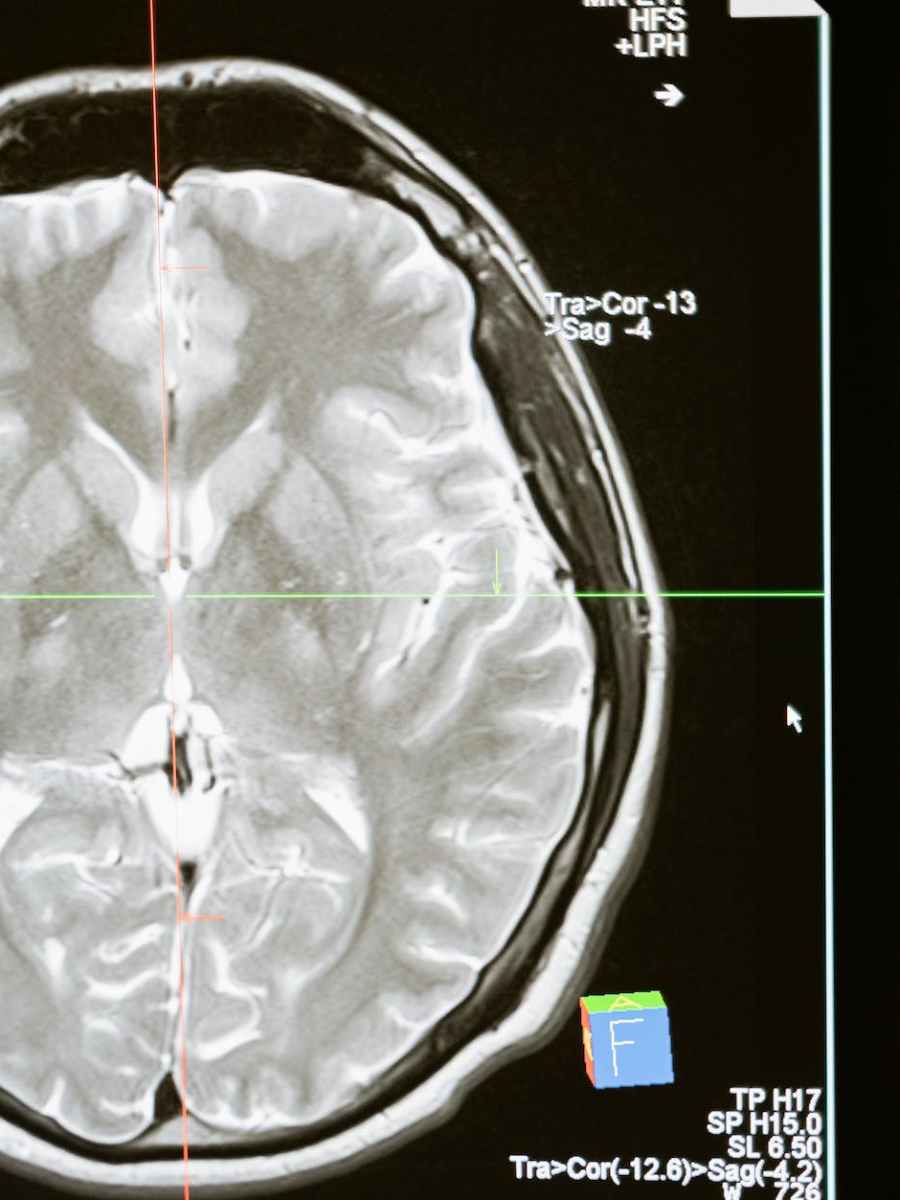

Why Antidepressants Take So Long to Work

WIRED A clinical trial reveals the first evidence of how the brain restructures physically in the first month on SSRIs—and the link between neuroplasticity and depression. CLINICAL DEPRESSION IS considered one of the most treatable mood disorders, but neither the condition nor the drugs used against it are fully understood. First-line SSRI treatments (selective serotonin…